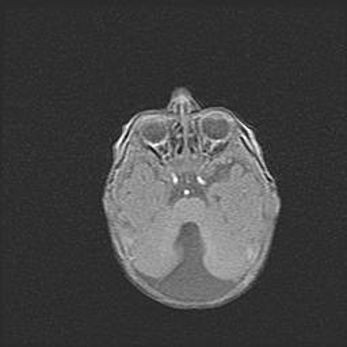

Мальформация Денди-Уокера. Киста задней черепной ямки.

Агенезия мозолистого тела.

Возраст: 2,5 месяца

Вес: 2420 г

Пол: женский

Окружность головы: 37 см

Срок гестации: 32 недели

Мальформация Денди—Уокера — редкий вид патологии ЦНС, представляющий собой врожденный порок развития каудального отдела ствола и червя мозжечка, ведущий к неполному раскрытию срединной (Мажанди) и латеральных (Лушка) апертур IV желудочка мозга. Для этогно синдрома характерна триада симптомов: гипотрофия червя мозжечка и/или полушарий мозжечка, кисты задней черепной ямки, гидроцефалия различной степени. В 70% случаев порок сочетается и с другими аномалиями головного мозга, в частности с агенезией мозолистого тела.